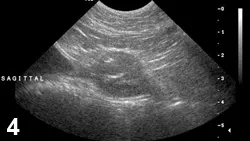

FIGURE 5

Prostatic adenocarcinoma. Sagittal image of an intact canine prostate showing characteristic BPH striations ventrally, but hypoechoic nodules (cursors) present within the dorsal parenchyma. Nonhomogenous prostatic parenchymal appearance should prompt evaluation with a biopsy.

• Multiple prostatic pathologies can be present in any patient (Figure 5).